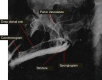

Retrograde urethrogram is employed for adequate demonstration of anterior urethral stricture and is commonly performed by trainee residents. Not uncommonly, contrast is injected under pressure to overcome the resistance of a stricture which can lead to extravasation or intravasation exposing the patient to risk of bacteremia, sepsis, contrast reactions, and worsening of stricture. We report two such cases of extensive intravasation delineating the "venogram" of peno-pelvic venous arcade. Such rare occurrences highlight the importance of eliciting history of various allergies and asthma, urethral instrumentation, obtaining sterile urine before the study, and performing the study under dynamic fluoroscopy.